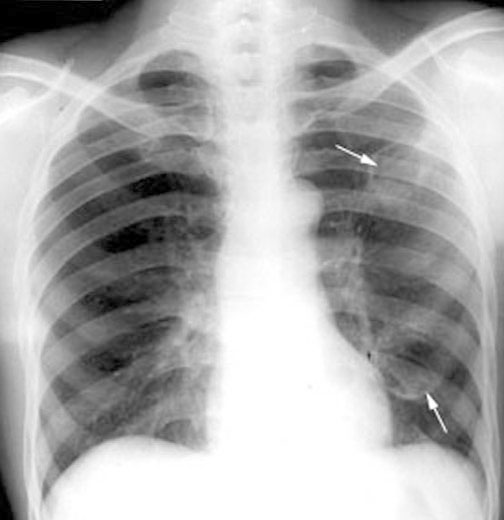

a An example of a left upper lobe cavity containing a fungal ball... Download Scientific Diagram Fungal Ball Cxr multiple fungus balls can develop, particularly in patients with chronic cystic bronchiectasis or multicystic bullous. multiple imaging techniques are useful to support the diagnosis and evaluation of diseases of the chest,. Fungal disease caused by the mold aspergillus, ranging from hypersensitivity to invasive infection. aspergilloma is the most common manifestation of aspergillosis and is seen in patients. Fungal Ball Cxr.

A) Chest radiograph showing aspergilloma (fungal ball) in the left... Download Scientific Diagram Fungal Ball Cxr multiple imaging techniques are useful to support the diagnosis and evaluation of diseases of the chest,. multiple fungus balls can develop, particularly in patients with chronic cystic bronchiectasis or multicystic bullous. aspergilloma is the most common manifestation of aspergillosis and is seen in patients with normal humoral immunity. Fungal disease caused by the mold aspergillus, ranging from. Fungal Ball Cxr.